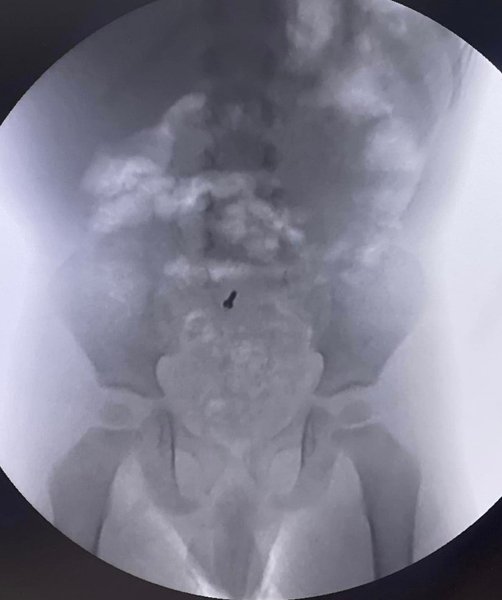

В сентябре 2022 года ему планировали сделать рентгенографию. Во время диагностического исследования медики и случайно зафиксировали в его брюшной полости металлический шуруп.

Врачи вместе с родителями решили наблюдать за мальчиком, не прибегая к медицинским манипуляциям и хирургическому вмешательству. Повторные рентгены показали, что посторонний предмет остался на месте.

Родители обратились к специалистам львовского "Охматдита". Колоноскопия шурупа не обнаружила, но впоследствии его нашли в аппендиксе. Врачи были удивлены, ведь такая ситуация наблюдается нечасто. После обнаружения находки ее сразу удалили.